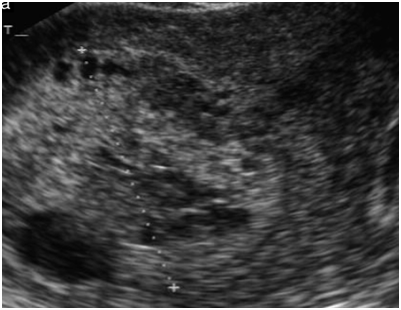

A total 1784 deliveries occurred at CHUK between January 2014 to December 2014. In the same study period, women presenting with signs or symptoms for GTD were evaluated at CHUK. GTD diagnosis was suspected by clinical exam, HCG and US findings. All patients received an ultrasound by an Obgyn resident and or faculty at the time of admission. Typical US findings of GTD included the presence of heterogeneous solid mass with hypoechoic cystic appearing lesion (Figure 1). US findings that demonstrated color flow into myometrium suggested invasive mole (GTN). Final diagnosis for GTD was confirmed by pathologic confirmation of either complete mole or partial mole. Twenty-seven patients were diagnosed with GTD. The prevalence of GTD at CHUK in 2014 was 1.5/1000 (Figure 2).

Figure 1 Honeycomb Sign.